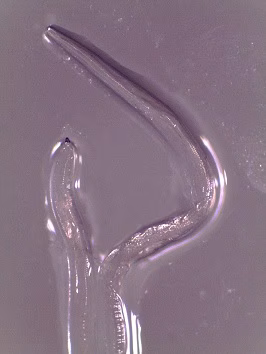

Adults of Thelazia spp. reside in the conjunctival sac of their definitive hosts, which are usually dogs or other canids, cattle, and horses; humans are usually only incidental hosts. Adults measure up to 2.1 cm in length. Thelazia species may be differentiated by the appearance of the cuticular striations, the depth and width of the buccal cavity, the placement of the vulval opening relative to the esophago-intestinal junction and the morphology of the tail and anal opening.